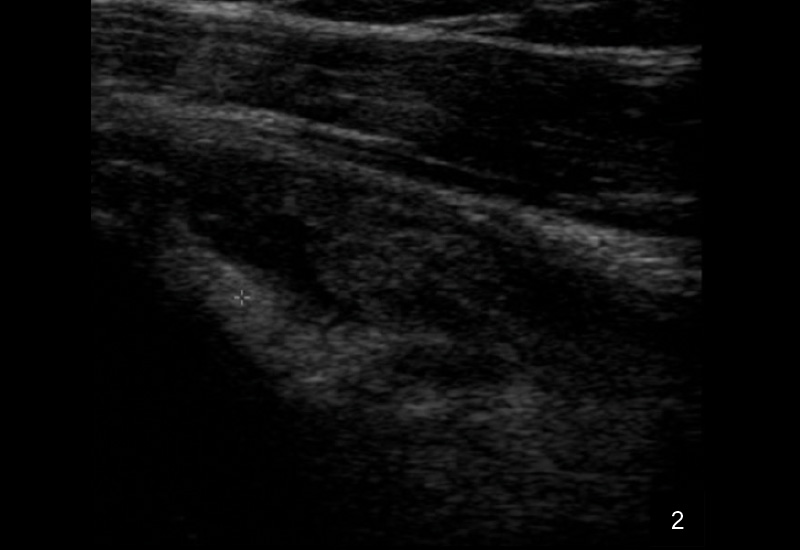

Die Sonografie gilt als erstes bildgebendes Verfahren hoher Wertigkeit bei der Diagnose einer Tenosynovitis der langen Bizepssehne, da sie dynamische Untersuchungen ermöglicht und periphere sowie intraartikuläre Abschnitte zuverlässig darstellt. Typische sonografische Kriterien umfassen eine Sehnenschwellung mit echoarmen Arealen, umgebende Flüssigkeitsansammlungen in der Sehnenscheide (Halo-Phänomen), synoviale Verdickungen und erhöhten Dopplerfluss als Hinweis auf Hypervaskularisation. Die Methode ist untersucherabhängig, bietet jedoch eine hohe Sensitivität (50–96 %) und Spezifität (bis 100 %) für Instabilitäten, Luxationen oder Rupturen, insbesondere durch Provokation in Außenrotation.